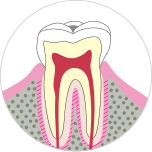

段階.C0

歯の表面からカルシウム等の無機成分が溶け出したごく初期の段階。

表面が白く濁ったり歯の溝が茶色になりますが、見た目はほどんど同じです。

主な症状

- ・表面が白く濁る

- ・溝が茶色になる

治療法

- ・フッ素を使って歯みがきをする

- ・歯科医院でのフッ素塗布